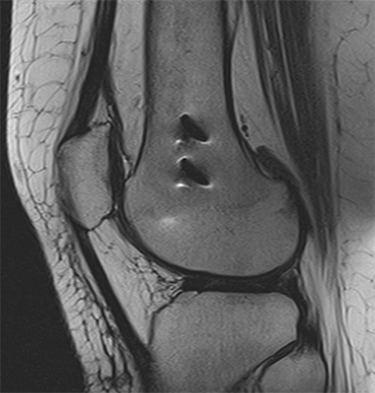

| Blurring or Ghosting Smearing in image | ![]() | Blurring and ghosting can be caused by patient motion, cardiac motion, or respiratory motion. |